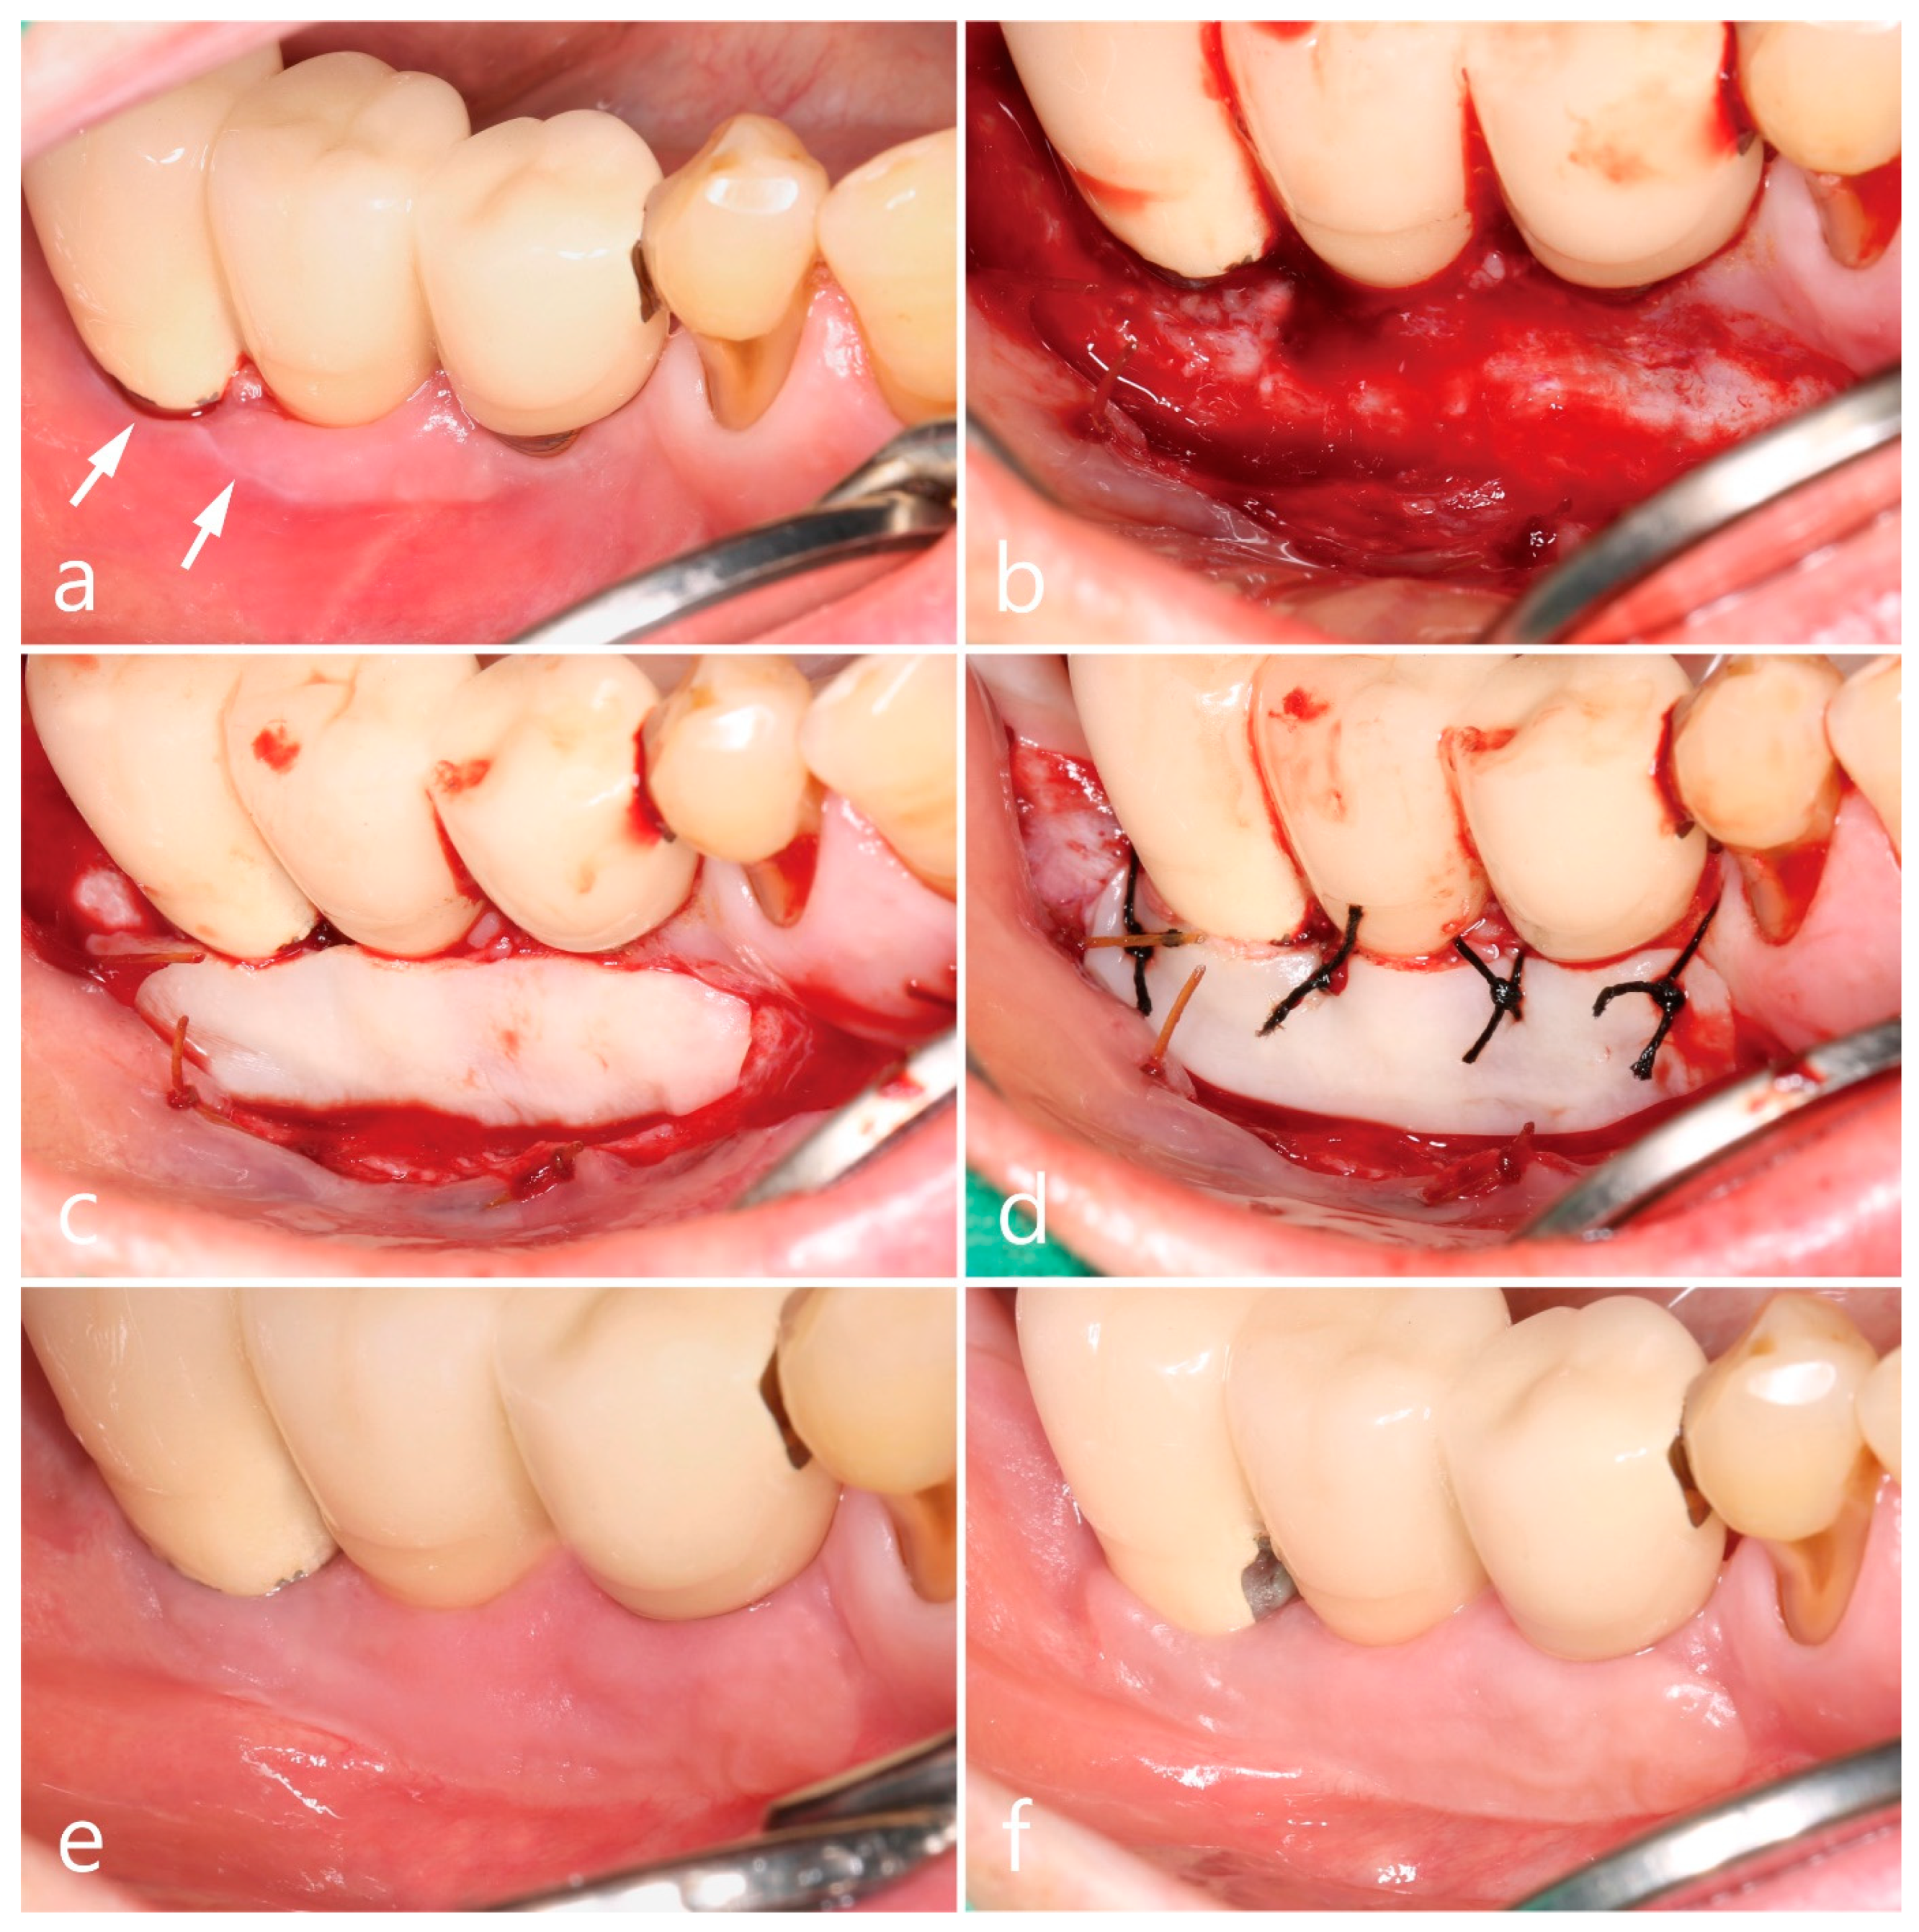

Figure 2.

Clinical aspects in the mandibular right posterior region. Oral lichenoid lesion with white striae (white arrows) (a), free gingival graft procedures (b–d), and postoperative follow-up for 3 months (e) and 10 years (f).

The second premolar, first and second molars in the right mandible were extracted and reconstructed as a cement-retained porcelain-fused-metal (PFM) three-unit bridge with two HA-coated implants (Steri-Oss® Inc., Yorba Linda, CA, USA) (Figure 1b). The patient complained of soreness upon contact with spicy or hot food and experienced discomfort while brushing in the buccal mucosal area around implants during a visit in 2002 after prosthesis placement. Clinical aspects of white striae and erythematous mucosa were observed, of which reticular type OLL was suspected, and the patient was referred to the Oral Medicine at the University Hospital for specialized management of the lesion. For palliative therapy, topical corticosteroid 0.1% dexamethasone ointment (Peridex, Green Cross Corp., Yongin, Republic of Korea) was repeatedly administered and recall visits were made every 2~3 weeks for 4 months; however, the improvement in symptoms was insignificant, and the lesion recurred continuously. In addition, the mandibular right posterior region had a shallow vestibule and lack of keratinized mucosa around implant prosthesis, which made the patient’s cleansing performance difficult. Therefore, a surgical approach involving keratinized tissue augmentation using FGG was performed, which resulted in the disappearance of OLL until the visit in 2011 (8 years after the first FGG). The patient’s attendance to the maintenance visit after the FGG was irregular, with 16~24 months of recall intervals. Self-performed mechanical plaque control in the interproximal areas of posterior teeth was not adequately done and easily showed bleeding on probing with plaque accumulation and gingival redness. At every visit, thorough whole-mouth scaling and root planing with an ultrasonic scaler (EMS, Nyon, Switzerland) and hand instrument were performed. However, advanced peri-implantitis was observed in both the premolar and second molar implants (Figure 1c), and the width of the grafted mucosa was significantly reduced after 3 months of implant removal. Three SLA surface implants (Implantium®, Dentium, Seoul, Republic of Korea) were placed and cement-retained PFM splinted crowns were delivered (Figure 1d), following which OLL recurred around the second molar region where the dimension of keratinized mucosa was almost lost (Figure 2a). White striae with erythematous surrounding in the buccal mucosa was observed. FGG was performed again around the mandibular right posterior implants to augment keratinized tissue around the implant and remove OLL concomitantly. Excision of the overlying mucosa, including the OLL, to leave only the periosteum, was performed during recipient bed preparation (Figure 2b). Epithelialized free gingival tissue measuring 25 × 6 × 1 mm was harvested from the opposite right maxillary palate and stabilized on the periosteum of the recipient bed (Figure 2c,d). An increase in keratinized mucosa with a deepened vestibule and relief of the OLL was observed after 3 months of healing (Figure 2e). To evaluate the pathologic tissue condition after the healing of FGG, intraoral clinical photography was taken under a standardized set and a scoring system with a four-point clinical grade scale (0–3) by Axéll and Henriksen [17] was applied. In short, it was subjectively assessed as grade 0 for no improvement or aggravation, grade 1 for improvement but with extensive erythema and/or symptoms, grade 2 for improvement but with some erythema and no symptoms, and grade 3 for healing with neither erythema nor symptoms. The healing score in the mandibular right region appeared to be grade 3, and a healthy mucosal condition was maintained for up to 10 years of follow-up (Figure 2f). Although the patient still showed irregular compliance for the recall visit, the interval was shortened within a year and professional mechanical plaque control was repeated for supportive maintenance therapy.